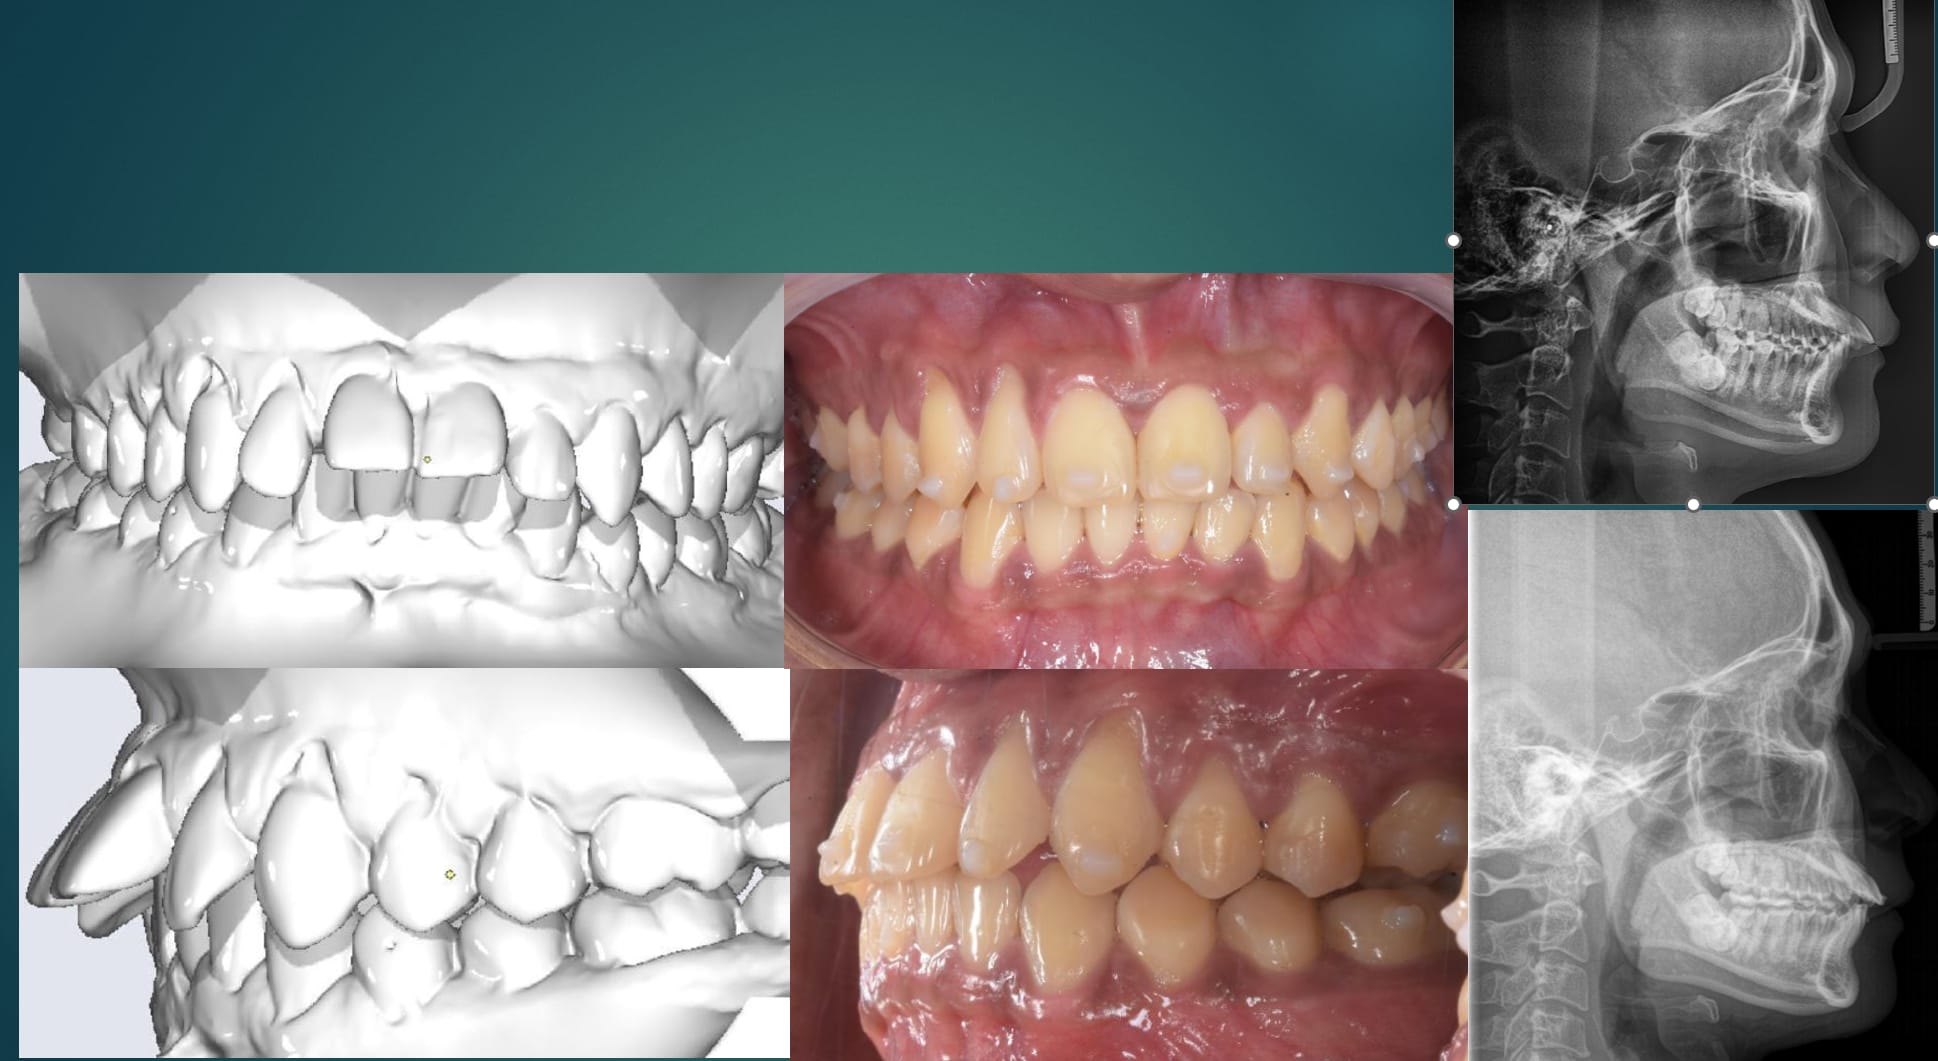

Regarde le cas posté plus haut, trois mois de progression, 50$ de cout total pour produire les aligneurs. Les deux attaches sur les canines sont à mon avis inutiles.

Les deux scans sur la second photo c'est un avant après envoyé par un étudiant. Sa clinique n'arrivait a rien avec ce cas et il y a avait quasi un attachement par dent. Le après c'est trois mois plus tard avec quasi pas d'attachement :-) .

Non, j'ai commencé le in-house ne mono couche , puis j'ai commencé à faire mes cas vraiment compliqué avec un plastique à splint à 0.5 centime la feuille ( deuxième photo , scan initiaux because les dentiste vietnamien à la clinique avait paumé les photos, et lat ceph avant après pour prouvé à des ortho US que j'avait bien fait une intrusion des secteurs ant et pas une extrusion des secteur post , ce qui aurait était plus impressionnant au passage ), maintenant je travaille en multi couche.

Les scans sont représentés en blanc, et les setups finaux de chaque série en couleur.

Première série (3 mois) :

L’objectif était de corriger l'articulé inversé par expansion et intrusion de la 22.

Le setup final (photo 1) montre une compensation intégrée avec une intrusion accentuée de la 22.

Le scan réalisé à la fin de la série montre la correction de l'articulé inversé, avec environ 50 % de l’intrusion planifiée réellement obtenue.

Deuxième série (2 mois) :

Cette phase visait à corriger la béance. Là encore, on observe une différence notable entre le setup final (photo 2) et le nouveau scan.

Si j’avais réalisé une seule série de 5 mois, le résultat aurait été nettement moins bon et aurait probablement conduit à un traitement plus long.

Cette variation dans le pourcentage de mouvement exprimé est l’un des facteurs qui expliquent pourquoi il est rarement efficace de planifier un traitement complet du début à la fin à partir d’un seul scan.